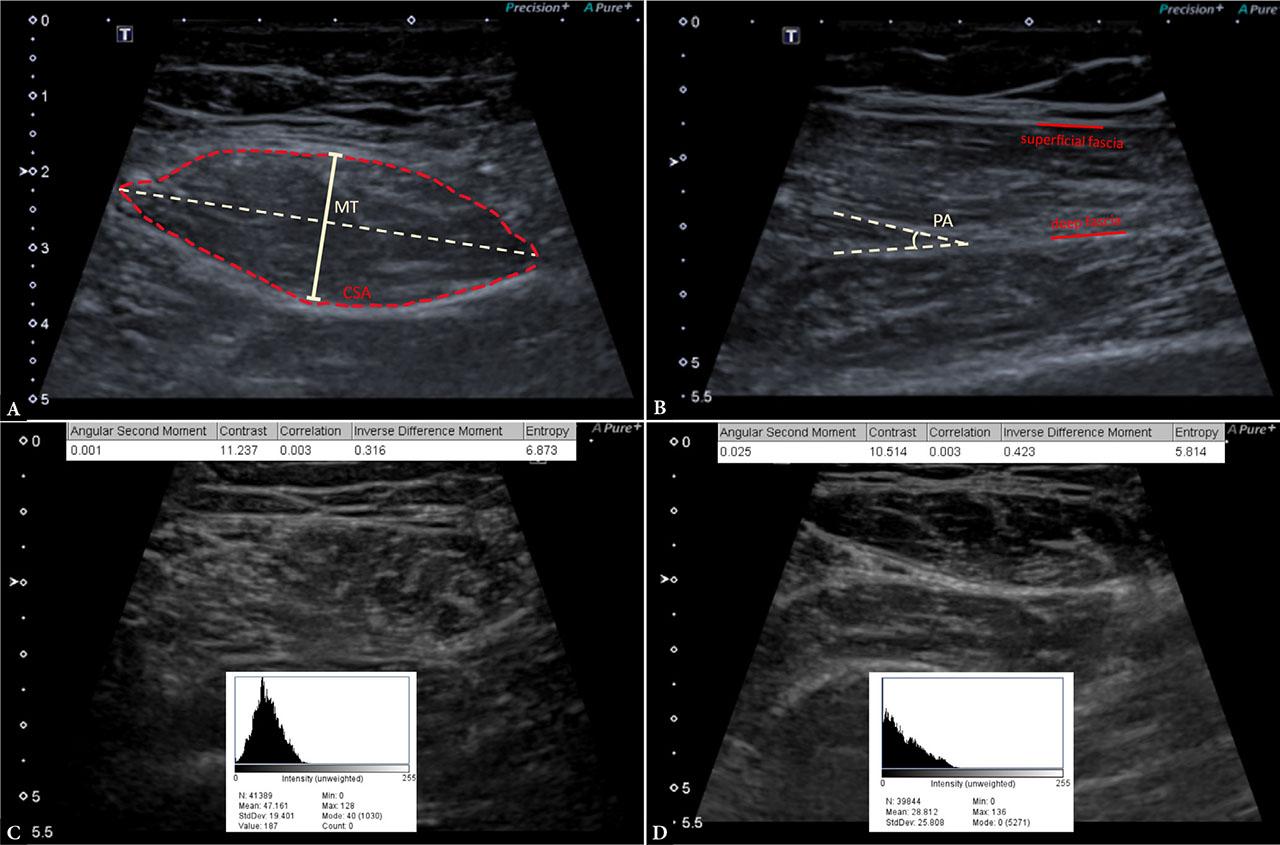

Ultrasound of the right rectus femoris (RF) muscle was performed using a Toshiba APLIO 400 ultrasound scanner (Canon; Tokyo, Japan), linear transducer (400 PLT-704AT), and built-in preset for the assessment of skeletal muscles with a penetration depth set at 5.5 cm and focus at 2.0 cm. Four trained investigators performed the ultrasound examinations and obtained measurements of muscle thickness (MT), cross-sectional area (CSA), and pennation angle (PA). Prior to study initiation, all four examiners independently acquired 15 skeletal muscle images from five pilot participants. These were then compared to ensure interrater agreement in image acquisition and measurement procedures. On the day of the examination, the same person who performed the ultrasound also conducted the CGA and entered the results into an online project database. However, CGA results remained blinded during data collection and were only unblinded at the end of the study during the final data analysis phase. Participants assumed the supine position and the ultrasound probe was placed perpendicular to the skin at the midpoint of the line connecting the anterior superior iliac spine to the upper edge of the patella. RF MT and CSA were measured in the short-axis view. The line of MT was drawn at the maximal vertical distance from the superficial to deep fascia layers, perpendicular to the femur (Fig. 1B). CSA was calculated using in-built software after manually outlining the muscle boundaries from the outermost fascia to the other edge. The above measurements were repeated during maximal voluntary RF contraction. In the long-axis view, PA was measured between the deep muscle fascia and the muscle fascicle using built-in angle-measuring software. Muscle fascicle length (FL) was estimated using the approved formula (Fig. 1A). We further analyzed ultrasound images in the ImageJ software (Version 1.52a, National Institute of Health, USA). One designated researcher, blinded to both CGA results and ultrasound size measurements, performed secondary analyses to extract muscle echogenicity and tissue texture features. Texture parameters were obtained using the gray-level co-occurrence matrix (GLCM) method (GLCM Texture Analyzer plugin v0.4, Julio E. Cabrera) (Tab. 1). A square region of interest (ROI) was placed within muscle tissue, avoiding surrounding fascia. The mean echogenicity of ROI was determined by grayscale analysis using the histogram function (Fig. 1C). All measurements were performed three times across different ultrasound images, and average values were used for analysis.

Example of ultrasound measurements of the rectus femoris (RF) muscle: A. the pennation angle (PA) was obtained in the long-axis view and measured between lines drawn along the deep muscle fascia and the muscle fascicle; b) RF thickness (MT) and cross-sectional area (CSA) were measured in the short-axis view, the former represented by the maximal vertical distance between the superficial and deep fascia layers, the latter calculated after outlining the muscle’s boundaries; C and D. echogenicity and gray-level co-occurrence matrix (GLCM) features were measured in the short-axis view: a square region of interest (ROI) was selected, and the following texture parameters were calculated using ImageJ software: mean pixel intensity, angular second moment (ASM), contrast, correlation, entropy, and inverse difference moment (IDM); C. muscle image from a patient in the “probable sarcopenia” group; D. muscle image from a patient in the “no probable sarcopenia” group